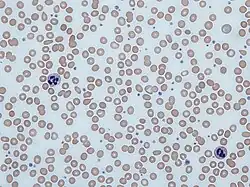

| Blood smear showing iron-deficiency anemia, with small, pale red blood cells | |

Anemia is typically diagnosed on a complete blood count. Apart from reporting the number of red blood cells and the hemoglobin level, the automatic counters also measure the size of the red blood cells by flow cytometry, which is an important tool in distinguishing between the causes of anemia. Examination of a stained blood smear using a microscope can also be helpful, and it is sometimes a necessity in regions of the world where automated analysis is less accessible.

Iron-deficiency anemia is the most common type of anemia overall, and it has many causes. RBCs often appear hypochromic (paler than usual) and microcytic (smaller than usual) when viewed with a microscope.